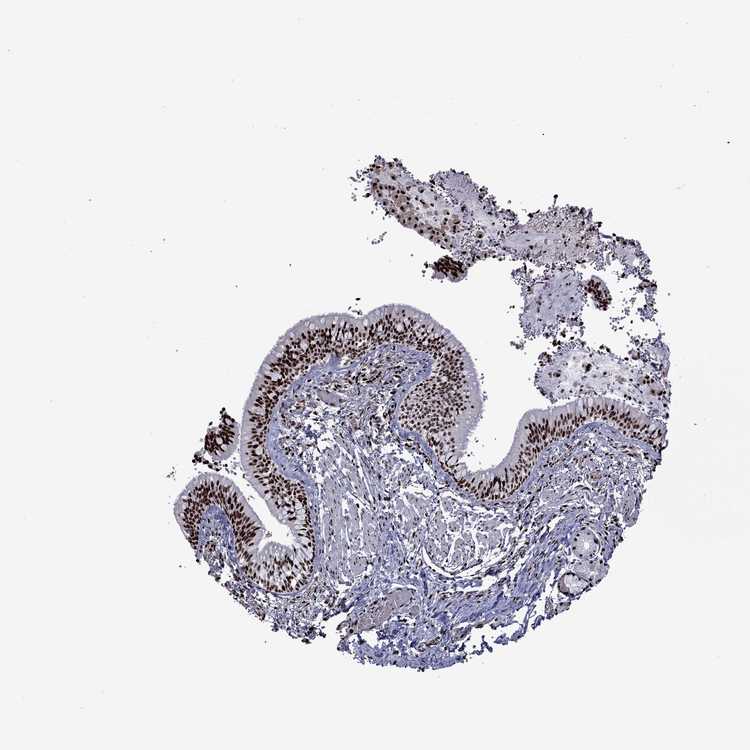

TISSUE PRIMARY DATA BRONCHUS Show tissue menu

Bronchus

BRONCHUS - Antibody stainingi

Antibody staining in the annotated cell types in the current human tissue is reported as not detected, low, medium, or high, based on conventional immunohistochemistry profiling in selected tissues. This score is based on the combination of the staining intensity and fraction of stained cells.

Each image is clickable and will lead to virtual microscopy that enables deeper exploration of all samples and also displays staining intensity scores, fraction scores and subcellular localization as well as patient and tissue information for each sample.

Antibody HPA028516Antibody HPA073571

Respiratory epithelial cells HighHigh